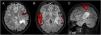

ObjetivoSe muestran 4 casos valorando la utilidad de la resonancia magnética funcional en el estudio prequirúrgico de pacientes con tumores neuroepiteliales disembrionarios. Para la obtención de imágenes se utilizó un equipo de resonancia magnética Philipps Intera de 3.0 Tesla y la técnica Blood Oxygenation Level-Dependent, permitiendo localizar las áreas elocuentes de lenguaje y motora mediante la aplicación de paradigmas específicos.

ResultadosEn un caso el tumor se encontraba adyacente al área de Broca, en 2 casos coincidía con Wernicke, en un paciente estaba menos de 1cm del área motora de la mano y en otro próximo a la memoria. Solo 2 de los pacientes fueron operados, no produciéndose déficit funcional postoperatorio. Se observó activación hemisférica contralateral al tumor sugestivo de neuroplasticidad en uno de los pacientes.

ObjectiveThis work aims to assess the usefulness of functional magnetic resonance imaging (fMRI) in the preoperative study in four patients with DNET. A Philips Intera 3.0 Tesla magnetic resonance imaging scanner and the Blood-Oxygen-Level-Dependent (BOLD) technique were used to obtain the images, making it possible to locate the eloquent areas for language and motor areas through the application of specific paradigms.

ResultsIn one case the tumour was adjacent to Broca's area, in two cases it coincided with Wernicke's area, in one patient it was<1cm from the motor area for the hand and in another close to memory. Only two of the patients were operated on, without postoperative functional deficit. Hemispheric activation contralateral to the tumour suggestive of neuroplasticity was observed in one of the patients.